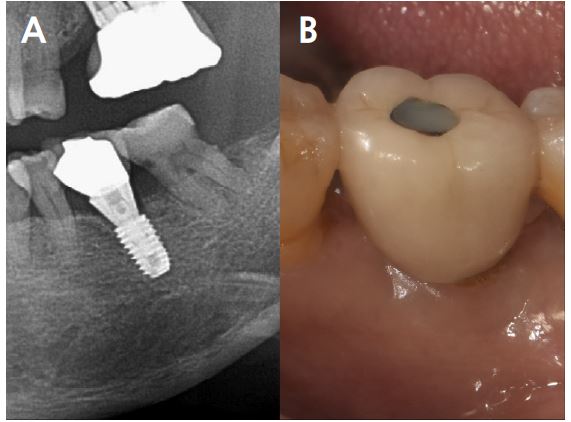

Five months after the first surgery of the implant, reopening for the second surgery, the site demonstrated that the fixture was surrounded by new bone, and hard bone quality was confirmed through a surgical curette. (Fig. 9A, 9B). The ISQ value at 2nd surgery was 73. Subsequently, a 6.0 mm diameter, 5 mm length healing abutment was placed (Fig. 10).

Follow-up CBCT view obtained after 2 years revealed that the bone and implant conditions were maintained without any complications for 19 months after prosthesis placement (Fig. 11A, 11B).